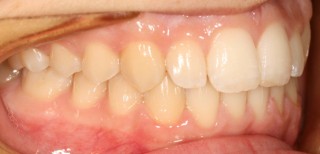

Um die Behandlung zu dokumentieren und für die Beratung der Patienten fertigen wir routinemäßig vor, nach und manchmal auf während der Behandlung Fotos von den Zähnen an.

Intraorales Bild02 [320x200] Intraorales Bild03 [320x200]